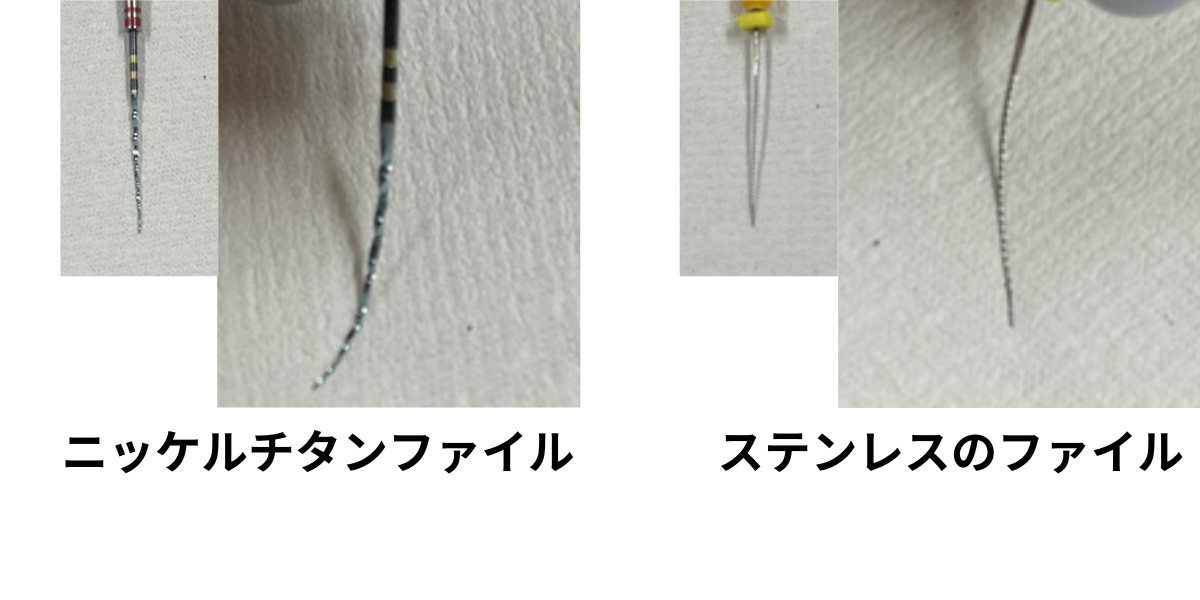

ニッケルチタンファイル

歯の神経の治療の際に、根の曲がりが強すぎると従来のステンレスの器具では根の先までのアクセスするために、歯の上部をより多く削らなければなりませんでした。

ニッケルチタンファイルを使用すると、根っこの形態が従来に比べてそのまま維持された状態で根の先にアクセスできるようになりました。

再治療の時など、根っこの形態が保存されているか否かで成功率に差が出てきます。

当院ではCTで根の状態を評価し必要に応じてニッケルチタンファイルを使用します。

ファイルの曲がり方の違い